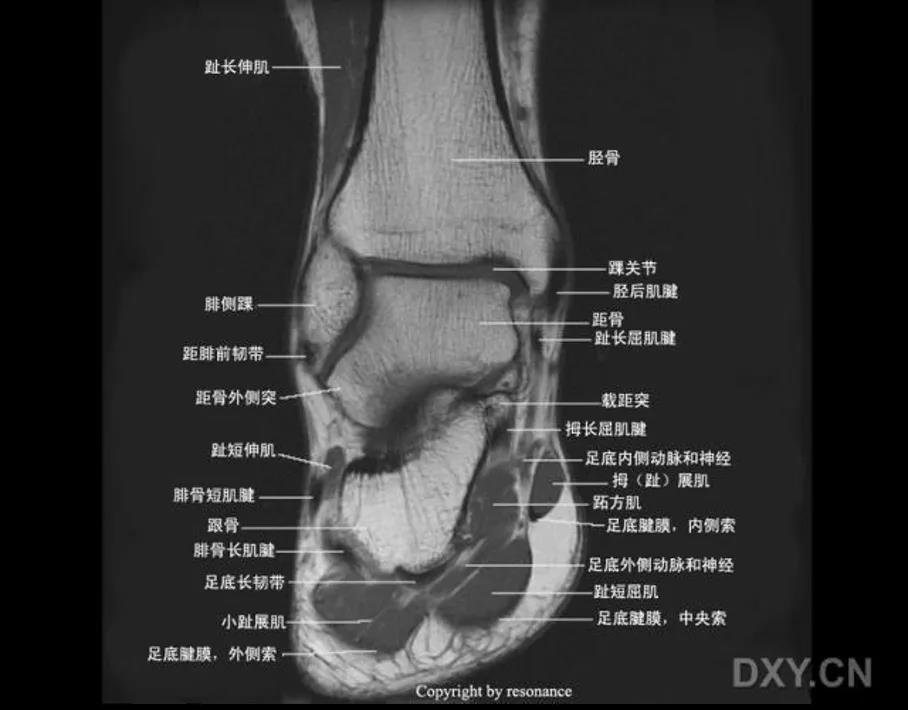

MRI:

三角韧带撕裂